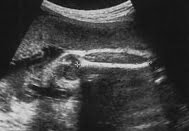

Fetal femur ölçümü normal değerleri

Hafta

alt sınır

(%5)

mm

Ortalama

(%50)

Üst sınır

(%95)